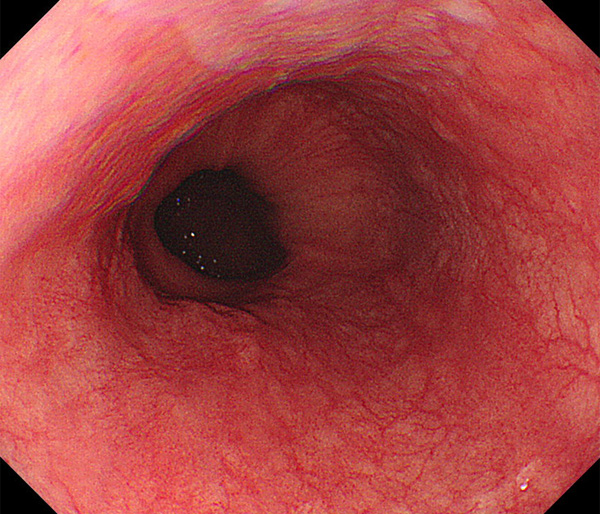

内視鏡所見と病理組織像の1対1対応が可能な症例を公募いたします。主にLSBEに発生した早期癌(HGDを含む)を対象としますが、興味深い症例であればSSBE癌でも結構です。採否は世話人へご一任ください。

症例呈示希望者は応募用紙に記入の上、代表的な内視鏡(2枚)、切除標本(新鮮、固定)、切り出し図、マッピング、代表的組織像とともに、Barrett 食道研究会事務局 barrett.shinshu@gmail.comへお申し込み下さい(10MB以下でお願い致します)。

特に、本邦では極めて稀なlong segment Barrett’s esophagus(LSBE)から発生した早期癌は、診断に難渋する場合も多く、欧米ではランダム生検による検出が標準的とされています。背景のBarrett食道もろとも全体を内視鏡切除+ラジオ波焼灼する欧米と異なり、ESDで内視鏡的な局所切除が基本の本邦では、存在診断+範囲診断(特に水平)を的確に行うことが不可欠です。

そのためには、一流の病理医による組織学的診断とエキスパート内視鏡医による拡大内視鏡像との一対一対応を徹底的に行うことで、『本来、見えないであろう拡大所見の先にある組織構築像が診えてくる』所まで内視鏡診断レベルを上げていく必要があります。その実現には、一対一対応を追究した症例(特にLSBE発生例)1例でも多く経験するしかありません。本研究会でBarrett食道腺癌(LSBE発生早期病変)を共に学び、拡大内視鏡像の一歩先を診るスキルを習得しましょう!一人でも多くの皆様のご参加をお待ちしています。